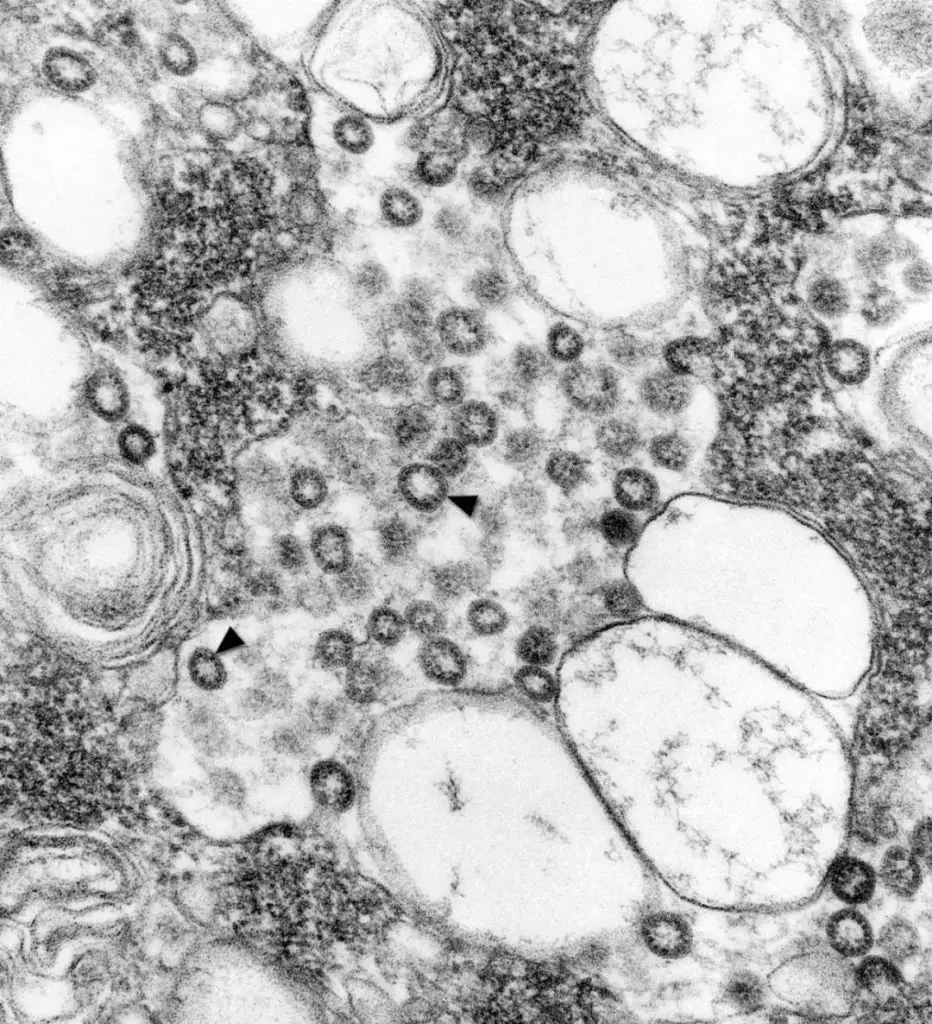

透射顯微鏡圖像:暗黑色圓形物的為新冠病毒。圖/NIAID-RML

NIAID表示,新冠病毒的圖像看起來和2012年暴發的MERS病毒以及2002年出現的SARS病毒很相似,這並不奇怪,因為這類病毒表面的突起物讓其擁有了「冠狀(corona)」的名稱,是“王冠(crown)”的拉丁文,所以,所有冠狀病毒基本都有這樣的形態特點。

2003年,SARS病毒剛剛暴發時,辛西婭從CDC拿到了病毒樣本,「這種病毒的表面缺少細節,看起來是一個普通的球體,通過透射電子顯微鏡的仔細觀察,從形態上可以認定它屬於冠狀病毒」。這一結論幫助CDC的專家迅速展開有針對性的冠狀病毒實驗。

黑色箭頭標註的就是SARS病毒。圖/CDC